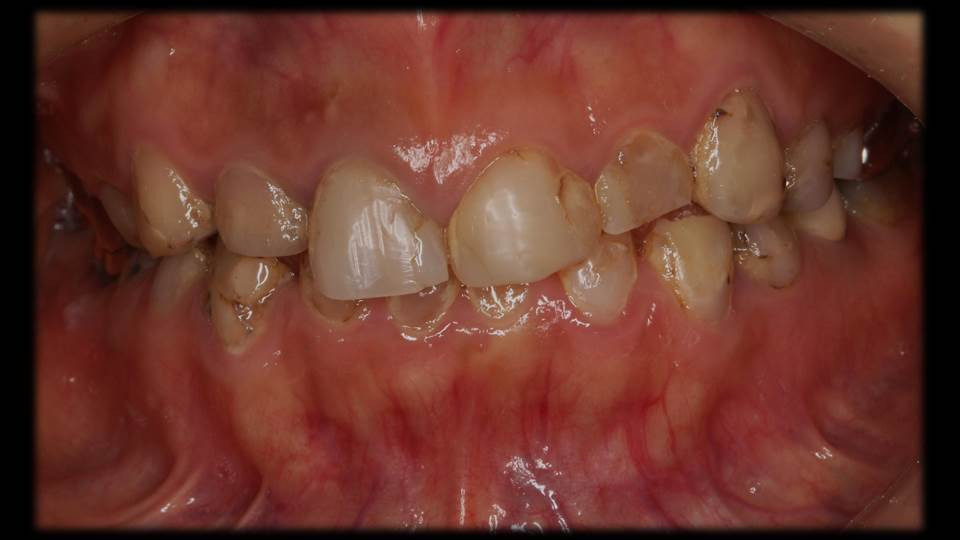

治療前のお口の中の様子①

下の前歯が小さくなっています。

酸性食品の過剰摂取胃酸の逆流現象で生じる口腔内の酸性化により「歯が溶ける」ことが近年分かってきました。嘔吐反射などがあると,特に下の前歯は胃液の強酸に曝露することが多く,写真のように歯が溶けて小さくなってしまうこともあります。

治療前のお口の中の様子②

お口全体のバランスが乱れています。

上下の歯を咬み合わせた状態です。お顔の正中のラインに揃えて写真を撮っているのですが,上下の歯の方向や歯茎ラインの乱れが生じた関係で,咬み合わせ歯並びを含めた口の中のバランスが悪くなっている状態です。金属アレルギーもあるため材料選択も制限がありましたが,セラミックス材料での咬合再構成の治療計画を立案しました。